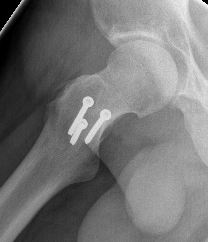

X-ray

Soft tissue swelling

Arthritic changes

Bone destruction

- invasion of adjacent metaphyseal cancellous bone

- may be suggestive of neoplasm

Bony involvement PVNS

Hip PVNS

Hip PVNS with erosions